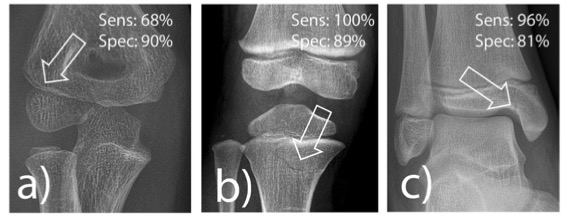

在我们的队列中(中位年龄 10.9 岁,59% 为男性),该人工智能表现出 92% 的敏感性、83% 的特异性和 87% 的准确性。对于具有法医学相关性的骨折,该人工智能对胫骨近端骨折的敏感性达到了 100%,但对桡骨髁骨折的敏感性仅为 68%。人工智能辅助将住院医师基于患者的敏感性从 84% 提高到 87%,特异性从 91% 提高到 92%,诊断准确性从 88% 提高到 90%。在 2% 的病例中,阅片者在人工智能的辅助下错误地放弃了他们原本正确的诊断。

图 根据van Laer,经常错过具有医学意义的骨折实体。a桡骨髁骨折,b胫骨近端骨折,c内踝骨折。用箭头标出的透光表示骨折